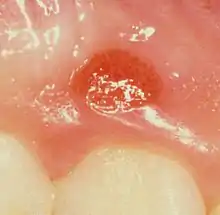

| Plasma cell gingivitis in an adult (histologically verified). | |

Plasma cell gingivitis appears as mild gingival enlargement and may extend from the free marginal gingiva on to the attached gingiva.[6] Sometimes it is blended with a marginal, plaque induced gingivitis, or it does not involve the free marginal gingiva. It may also be found as a solitude red area within the attached gingiva (pictures). In some cases the healing of a plaque-induced gingivitis or a periodontitis resolves a plasma cell gingivitis situated a few mm from the earlier plaque-infected marginal gingiva. In case of one or few solitary areas of plasma cell gingivitis, no symptoms are reported from the patient. Most often solitary entities are therefore found by the dentist.[2]

The gums are red, friable, or sometimes granular, and sometimes bleed easily if traumatised.[6] The normal stippling is lost.[7] There is not usually any loss of periodontal attachment.[6] In a few cases a sore mouth can develop, and if so pain is sometimes made worse by toothpastes, or hot or spicy food.[7] The lesions can extend to involve the palate.[7]